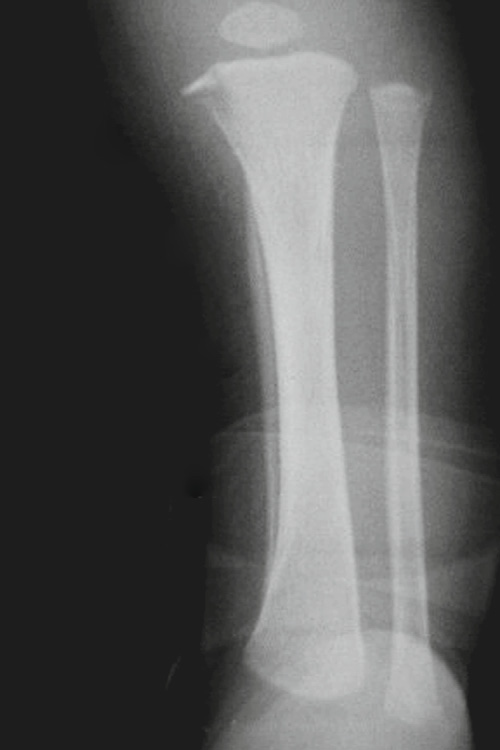

Toddler’s fracture

• When a child first begins to walk

• A nondisplaced oblique or spiral fracture of the midshaft

of the tibia

• Most children present with failure to continue to walk or refusal to bear weight on that extremity